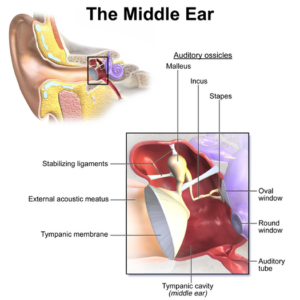

Acute Otitis Media (AOM)

Images

1